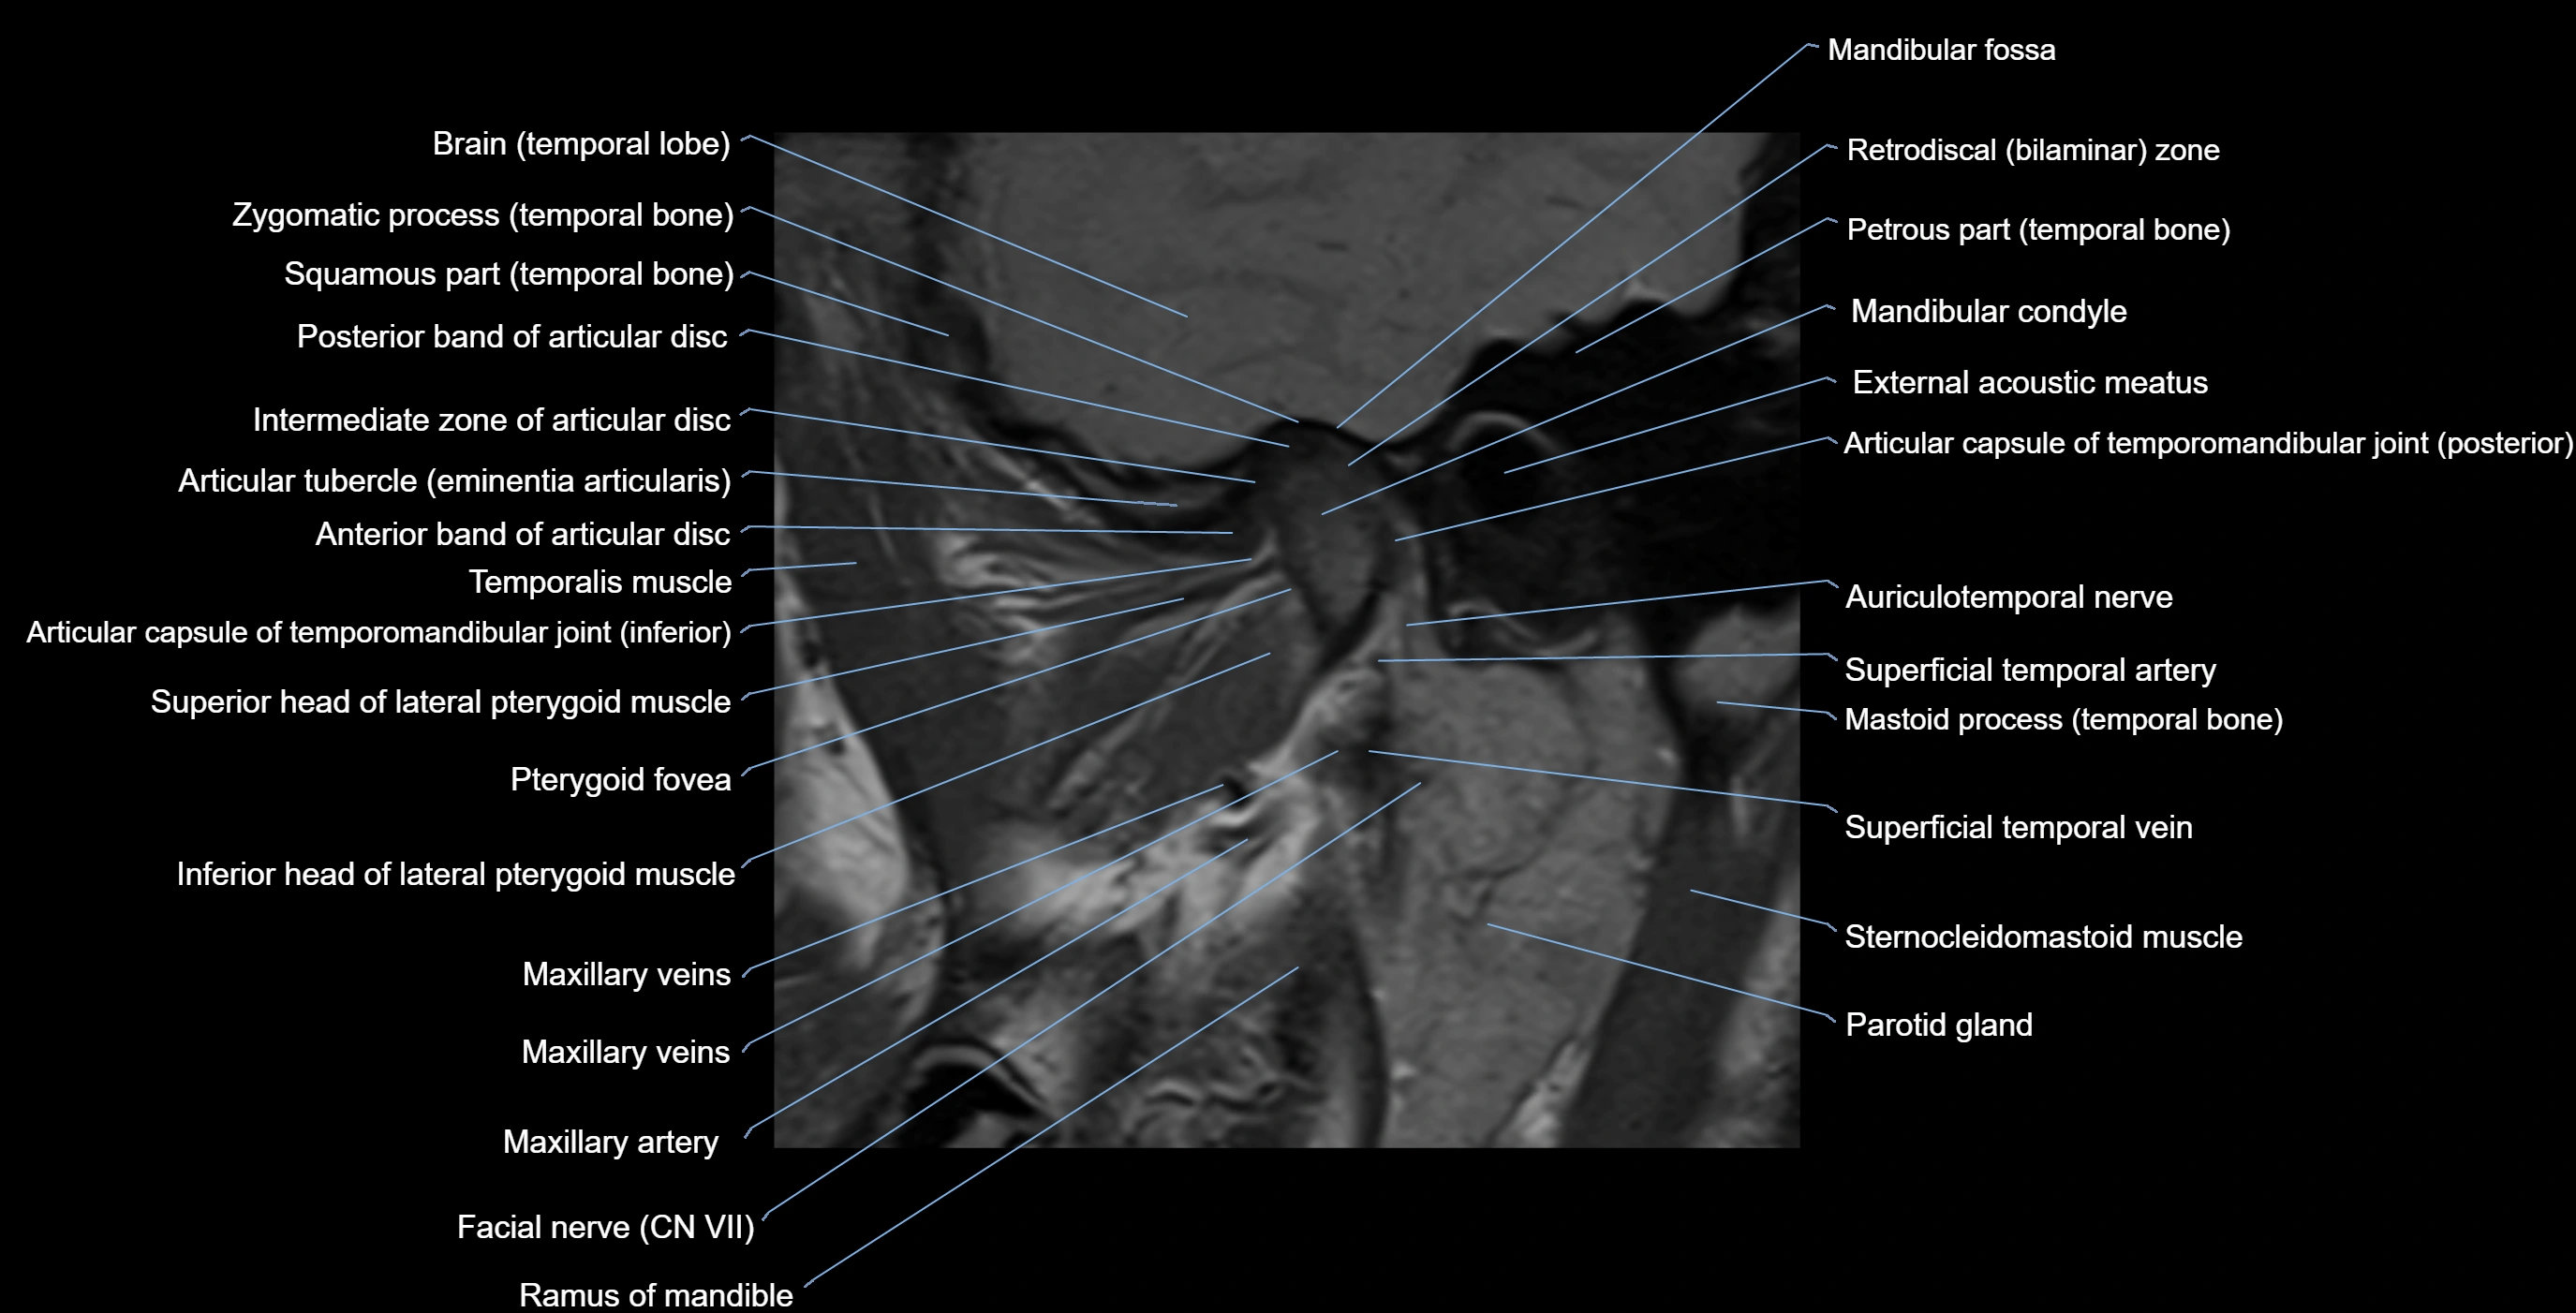

MRI appearance

T1-weighted images:

• Cortical bone: Low signal intensity

• Cancellous marrow: Intermediate to high signal depending on fatty content

• Teeth: Signal void structures

• Adjacent soft tissues: Normal gingiva and oral mucosa signal

T2-weighted images:

• Cortical bone and teeth: Low signal

• Marrow: Intermediate signal